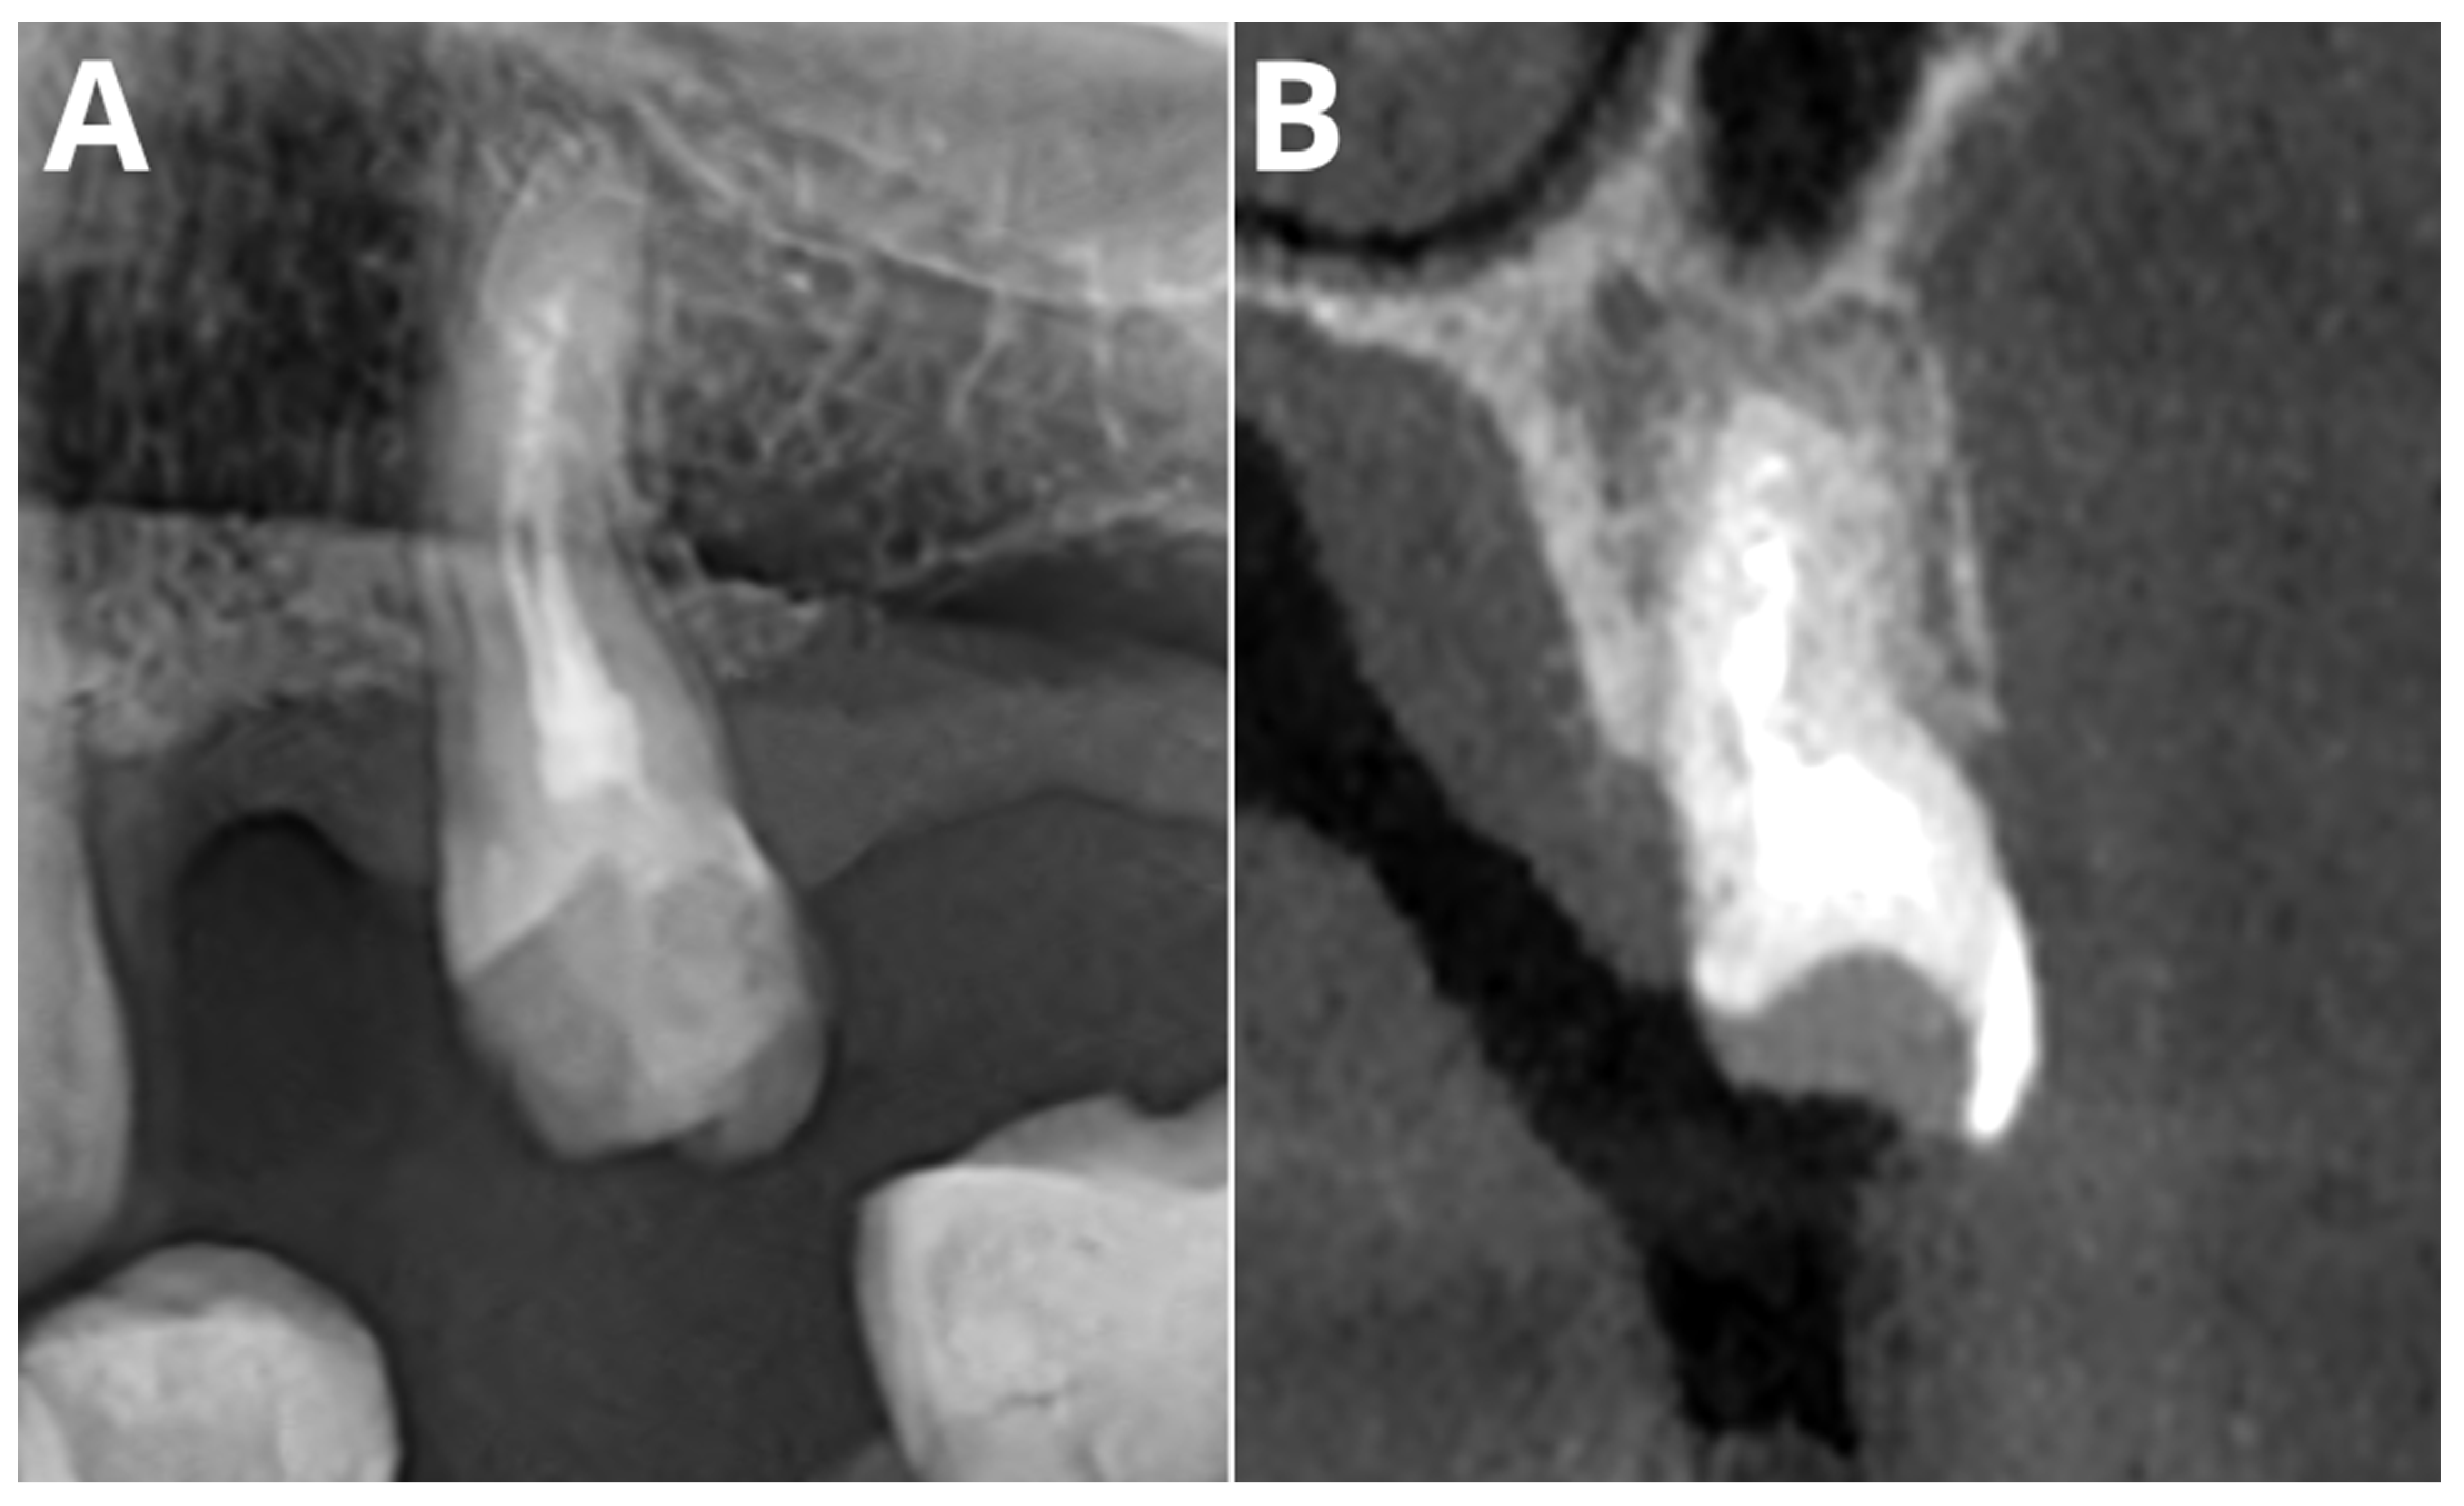

2. Materials and Methods

2.2. Image Acquisition and Post-Processing

2.3. Multireader Evaluation

2.4. AI Evaluation